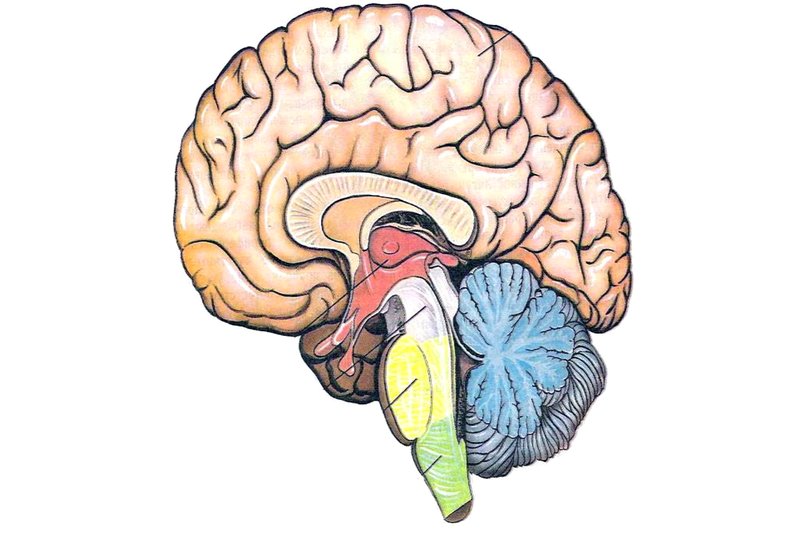

Легкие рисунки головного мозга: Пошаговые инструкции

Раздел: Житейские мотивы